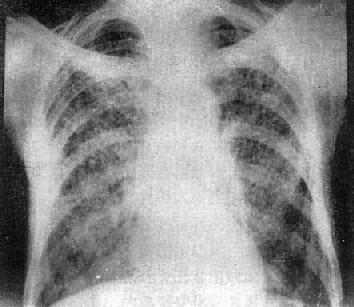

(1)一侧性肺不张:X线现为患侧肺野均匀致密,纵隔向患侧移位,肋间隙变窄(图3-1-7)。健侧肺可有代偿性肺气肿。

图3-1-7 一侧性肺不张

左侧支气管阻塞引起左侧全肺不张,显示左侧肺野均匀致密,

纵隔向患侧移位,肋间隙变窄,膈升高